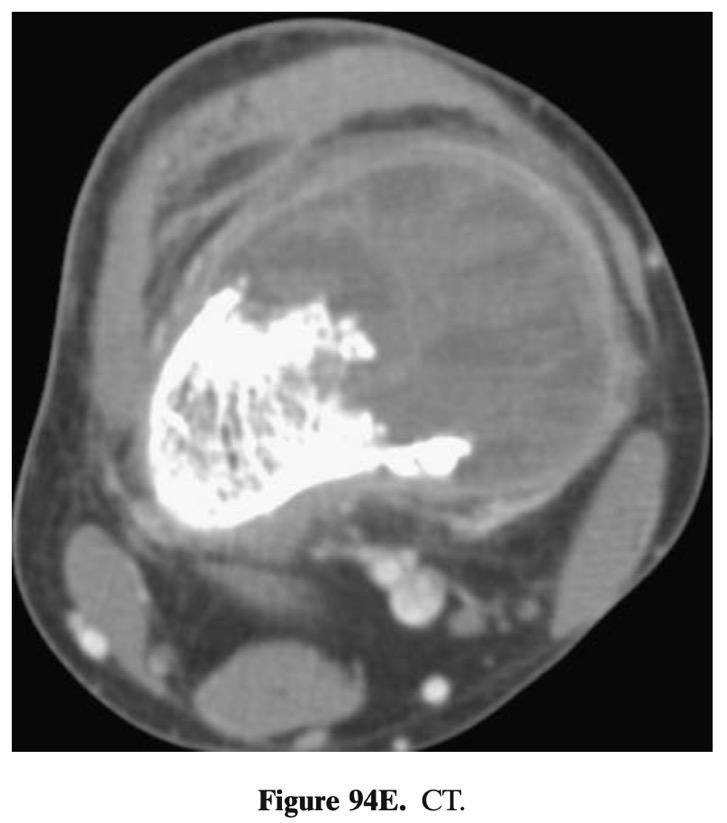

- ostéolytique mais 58% avec calcification périphérique (85% vue en CT: 94E)